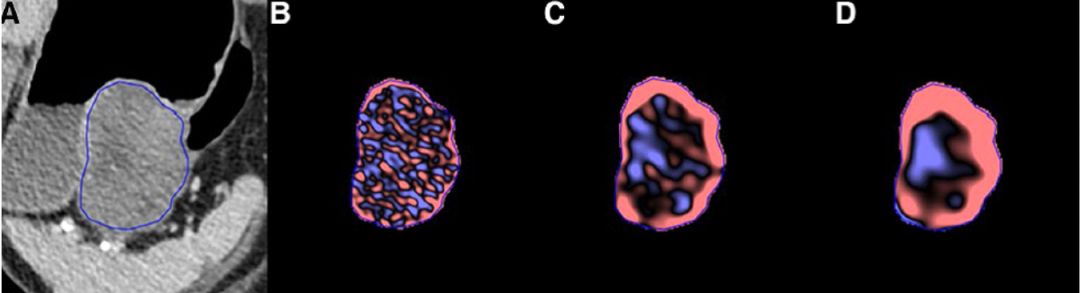

3. 双能CT预测GIST危险度分级

Gastrointestinal stromal tumor risk classification: spectral CT quantitative parameters

Xueling Zhang,Liangcai Bai,Dan Wang,Xiaoyu Huang,Jinyan Wei,Wenjuan Zhang,Zhuoli Zhang,Junlin Zhou

Abdominal Radiology.

https://doi.org/10.1007/s00261-019-01973-w

IF:1.842

摘要】

目的:探讨双能CT定量参数评价胃肠间质瘤(GIST)危险度分级的价值。材料和方法:本回顾性研究由机构审查委员会批准。签署知情同意书。纳入86例病理证实的GIST患者(30例高风险、22例中风险、28例低风险和6例极低风险;平均年龄:59岁[范围19-83岁])进行评估,这些患者从2015年3月至2017年9月接受了平扫和三期增强双能CT成像检查。定量

参数包括70kev单能图像CT值、能谱曲线斜率、标准化碘浓度(nic)和水(碘)浓度值,并进行了效能检验。

结果:(1)高危险组70 kev的CT值在各增强时相均高于中、低危险组(P<0.001),中、低危险组间无显著性差异(P=0.874,0.871,0.831)。(2)高危险组的能谱曲线斜率在各增强时相均高于中、低危险组(P<0.001),中、低危险组之间无显著性差异(P=0.069,0.466,0.840)。(3)高危险组与低危险组的NIC差异显著(P≤0.001)。中、低危组无显著性差异(P=0.671,0.457,0.833)。(4)效能检验结果表明,只有延迟期低危险组为0.530,其余组均大于0.999。

结论:双能CT定量分析有助于提高术前预测GIST病理危险度分类的准确性,但中、低危险组的区分存在局限性。

北京大学肿瘤医院

医学影像科 唐磊教授

GIST危险度预测已然成为近年来GIST影像学研究的绝对热点,上篇应用了机器纹理分析技术,本篇应用的则是CT技术最新里程碑的双能CT。双能CT借助双球管或单球管电压快速切换技术,可模拟出101个keV的连续单能CT图像,单能图像除了具有更高分辨率,多能量值也可计算得到一些定量参数,如能量曲线、碘浓度值等,较半定量的CT值又有了进一步的提升。既往已有类似研究探讨过能量CT在GIST诊断、分级及疗效评价的应用。本文利用几个双能CT参数区分出了高危和非高危两类GIST,可惜未与体积、形态、异质性等常规特征进行比较,进一步证实新技术参数相对于传统手段的价值。

1. 应用CT纹理分析参数预测GIST的危险度:与主观参数的比较

Feasibility of using computed tomography texture analysisparameters as imaging biomarkers for predicting risk gradeof gastrointestinal stromal tumors: comparison with visual inspection

In Young Choi, Suk Keu Yeom, Jaehyung Cha, Sang Hoon Cha, Seung Hwa Lee, Hwan Hoon Chung,

Chang Min Lee, Jungwoo Choi

Abdominal Radiology. https://doi.org/10.1007/s00261-019-01995-4

【摘要】

目的:通过与主观判断的比较,评价CT纹理分析(CTTA)参数预测胃肠间质瘤GIST危险度分级和核分裂像的可行性。方法和材料:对145例手术证实的GIST(平均尺寸:42.9±37.5 mm),使用TexRad软件,在空间比例因子(SSF)2-6,平均值、标准差、熵、正性像素平均值(MPP)、偏度和峰度,与危险分级和核分裂像及主观判断有无坏死进行比较。建立CTTA参数与危险度分级的相关性。ROC曲线判断诊断效能。由两名研究者主观判断强化模式、坏死、异质性、钙化、生长方式及黏膜溃疡。结果:三到四个不同尺度的参数在不同的危险度等级、核分裂像和有无坏死间存在明显差异(P<0.041)。中细度的MPP(r=-0.547至-393)和粗尺度的峰度(r=0.424-0.454)与危险等级显著相关(P<0.001)。SSF 2的MPP(AUC,0.782)和SSF 4的峰度(AUC,0.779)(所有P<0.001),区分HG-GIST与LG-GIST最佳。在增强图像上,HG-GIST的CT密度低或等于竖脊肌(OR 2.1;P=0.037;AUC,0.59)、坏死(OR,6.1;P<0.001;AUC,0.70)、异质性(OR,4.3;P<0.001;AUC,0.67)和粘膜溃疡(OR,3.3;p=0.002;AUC,0.62)。结论:应用TexRad,MPP和峰度可有效预测GIST的危险度等级和核分裂像。CTTA展示出在术前GIST危险度分层的价值。

CT图像纹理分析预测GIST危险度的又一项研究,入组病例百例以上,但最终的结果并不是特别理想,纹理特征区分危险度的AUC值均不足0.8;尽管已经高于主观参数(0.6-0.7)。本研究和之前报道的研究结果也有不一致之处,比如熵值在两组间未出现差异。本研究应用的TexRAD软件,既往有文献报道应用该软件CTTA在不一致的CT技术间,包括层厚、管电流、电压等,会有较高的鲁棒性。另外,文章给出了纹理分析的伪彩图,是既往文献中较为少见的,也使我们得以窥见纹理分析的真容。